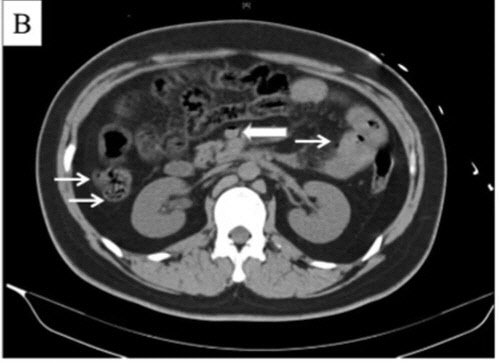

가는 화살표는 내장에 가스가 차 있음을 보여주고, 굵은 화살표는 내장에서 간으로 혈액을 운반해주는 혈관에 장간막 정맥에 가스가 차 있음을 보여준다. 국제 과학, 건강 전문 분석 회사 엘스비어(Elsevier).

또 CT(컴퓨터단층촬영) 검사 결과 그의 장기와 간문맥(장과 간 사이의 혈관)에 평소와 달리 가스가 차 있었고, 간에서는 산소 공급 부족으로 장기가 손상되는 '허혈' 증세도 나타났다.